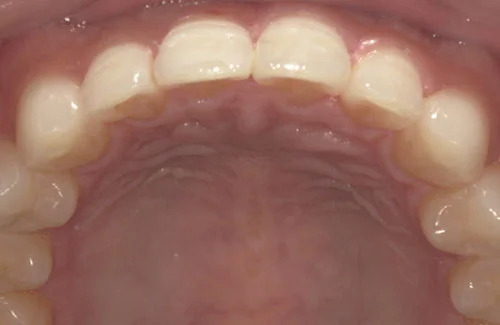

<症例7>歯がガタガタで噛み合わせが悪くお悩み

抜歯無し・マウスピースのみで矯正した症例です。

もともと歯列弓が非常に狭く、V字に近い形をしていたので噛み合わせも非常に不安定でした。

また、下顎前歯部がかなり上の方に生えていたため、下の前歯が上の前歯を突き上げてしまい出っ歯の状態になっていました。

現在では見た目はもちろん、臼歯の噛み合わせも改善しております。

患者様と症状

主訴:歯のガタガタ、噛み合わせが悪い

性別・年齢:20代女性

問題点:叢生(重度)、V字歯列弓、ディープバイト

診断:前歯部の叢生を伴うアングルⅠ級、骨格性Ⅰ級の不正咬合

主なリスク:臼歯の移動に伴い一時的に咬合しにくくなる、歯肉退縮

症状:叢生(そうせい) 過蓋咬合(かがいこうごう)

治療内容

治療期間:1年10ヶ月

治療費用:990,000円(税込)

プラン:Full2プラン

抜歯:無し

再診治療費:無し

追加治療費:無し

保定装置費:無し

治療前後の写真